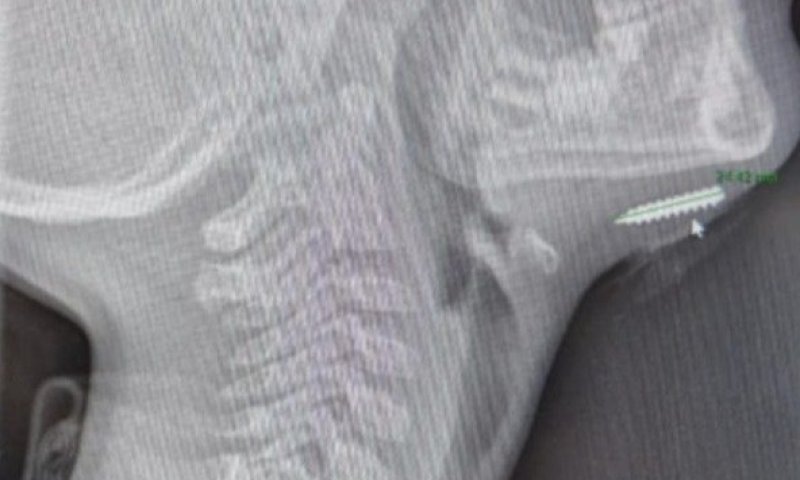

הבדיקה העלתה חשד לגוף זר בעומק הרקמה. צילום רנטגן שבוצע מיד לאחר מכן חשף את גודל ההפתעה: בורג קטום באורך של כשני סנטימטרים

ד"ר בשיר נסראללה, מומחה ברפואה דחופה בילדים במרכז הרפואי בני ציון, ערך בדיקת אולטרסאונד (POCUS) ליד מיטת הילד והבדיקה העלתה חשד לגוף זר בעומק הרקמה. צילום רנטגן שבוצע מיד לאחר מכן חשף את גודל ההפתעה: בורג קטום באורך של כשני סנטימטרים היה נעוץ בתוך סנטרו של הילד.

מנהל מחלקת ילדים במרכז הרפואי בני ציון, פרופ' יעקב גניזי: "בפעולה מתואמת עם מומחי אף־אוזן־גרון במרכז הרפואי בני ציון הוצא הבורג בשלמותו, ולאחר מכן נתפר הפצע".